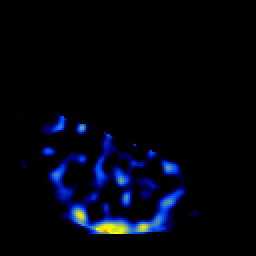

SPECT TL Study #6 -- Slice #15

[Home][Help][Clinical][Tour 1][Tour 2][Tour 3] Slice 15